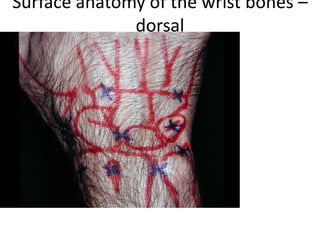

- Naming the bones, joints, tendons, nerves and skin landmarks of the hand and wrist.